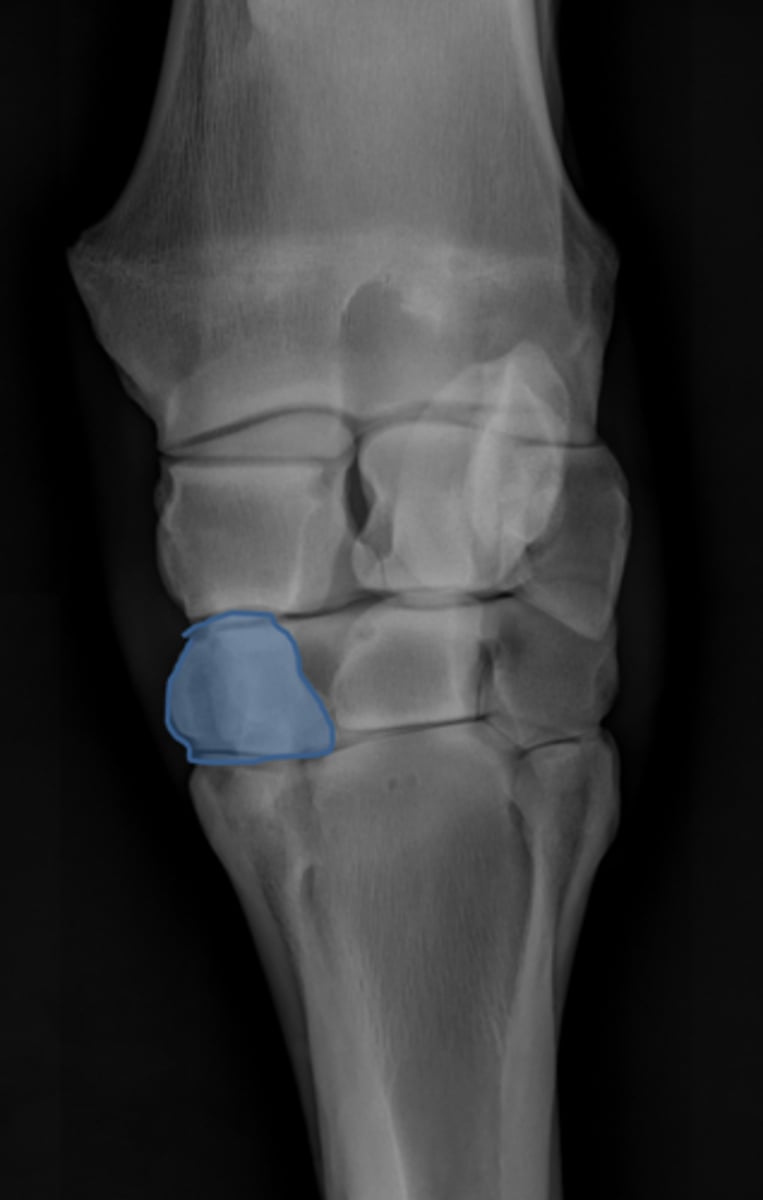

Carpus, lateral

ID joint and view

Antebrachiocarpal joint

Middle carpal joint

Carpometacarpal joint

Radial carpal bone

Intermediate carpal bone

Ulnar carpal bone

Third carpal bone

Second carpal bone

Fourth carpal bone

Accessory carpal bone

Second metacarpal (medial splint)

Fourth metacarpal (lateral splint)

Cannon bone